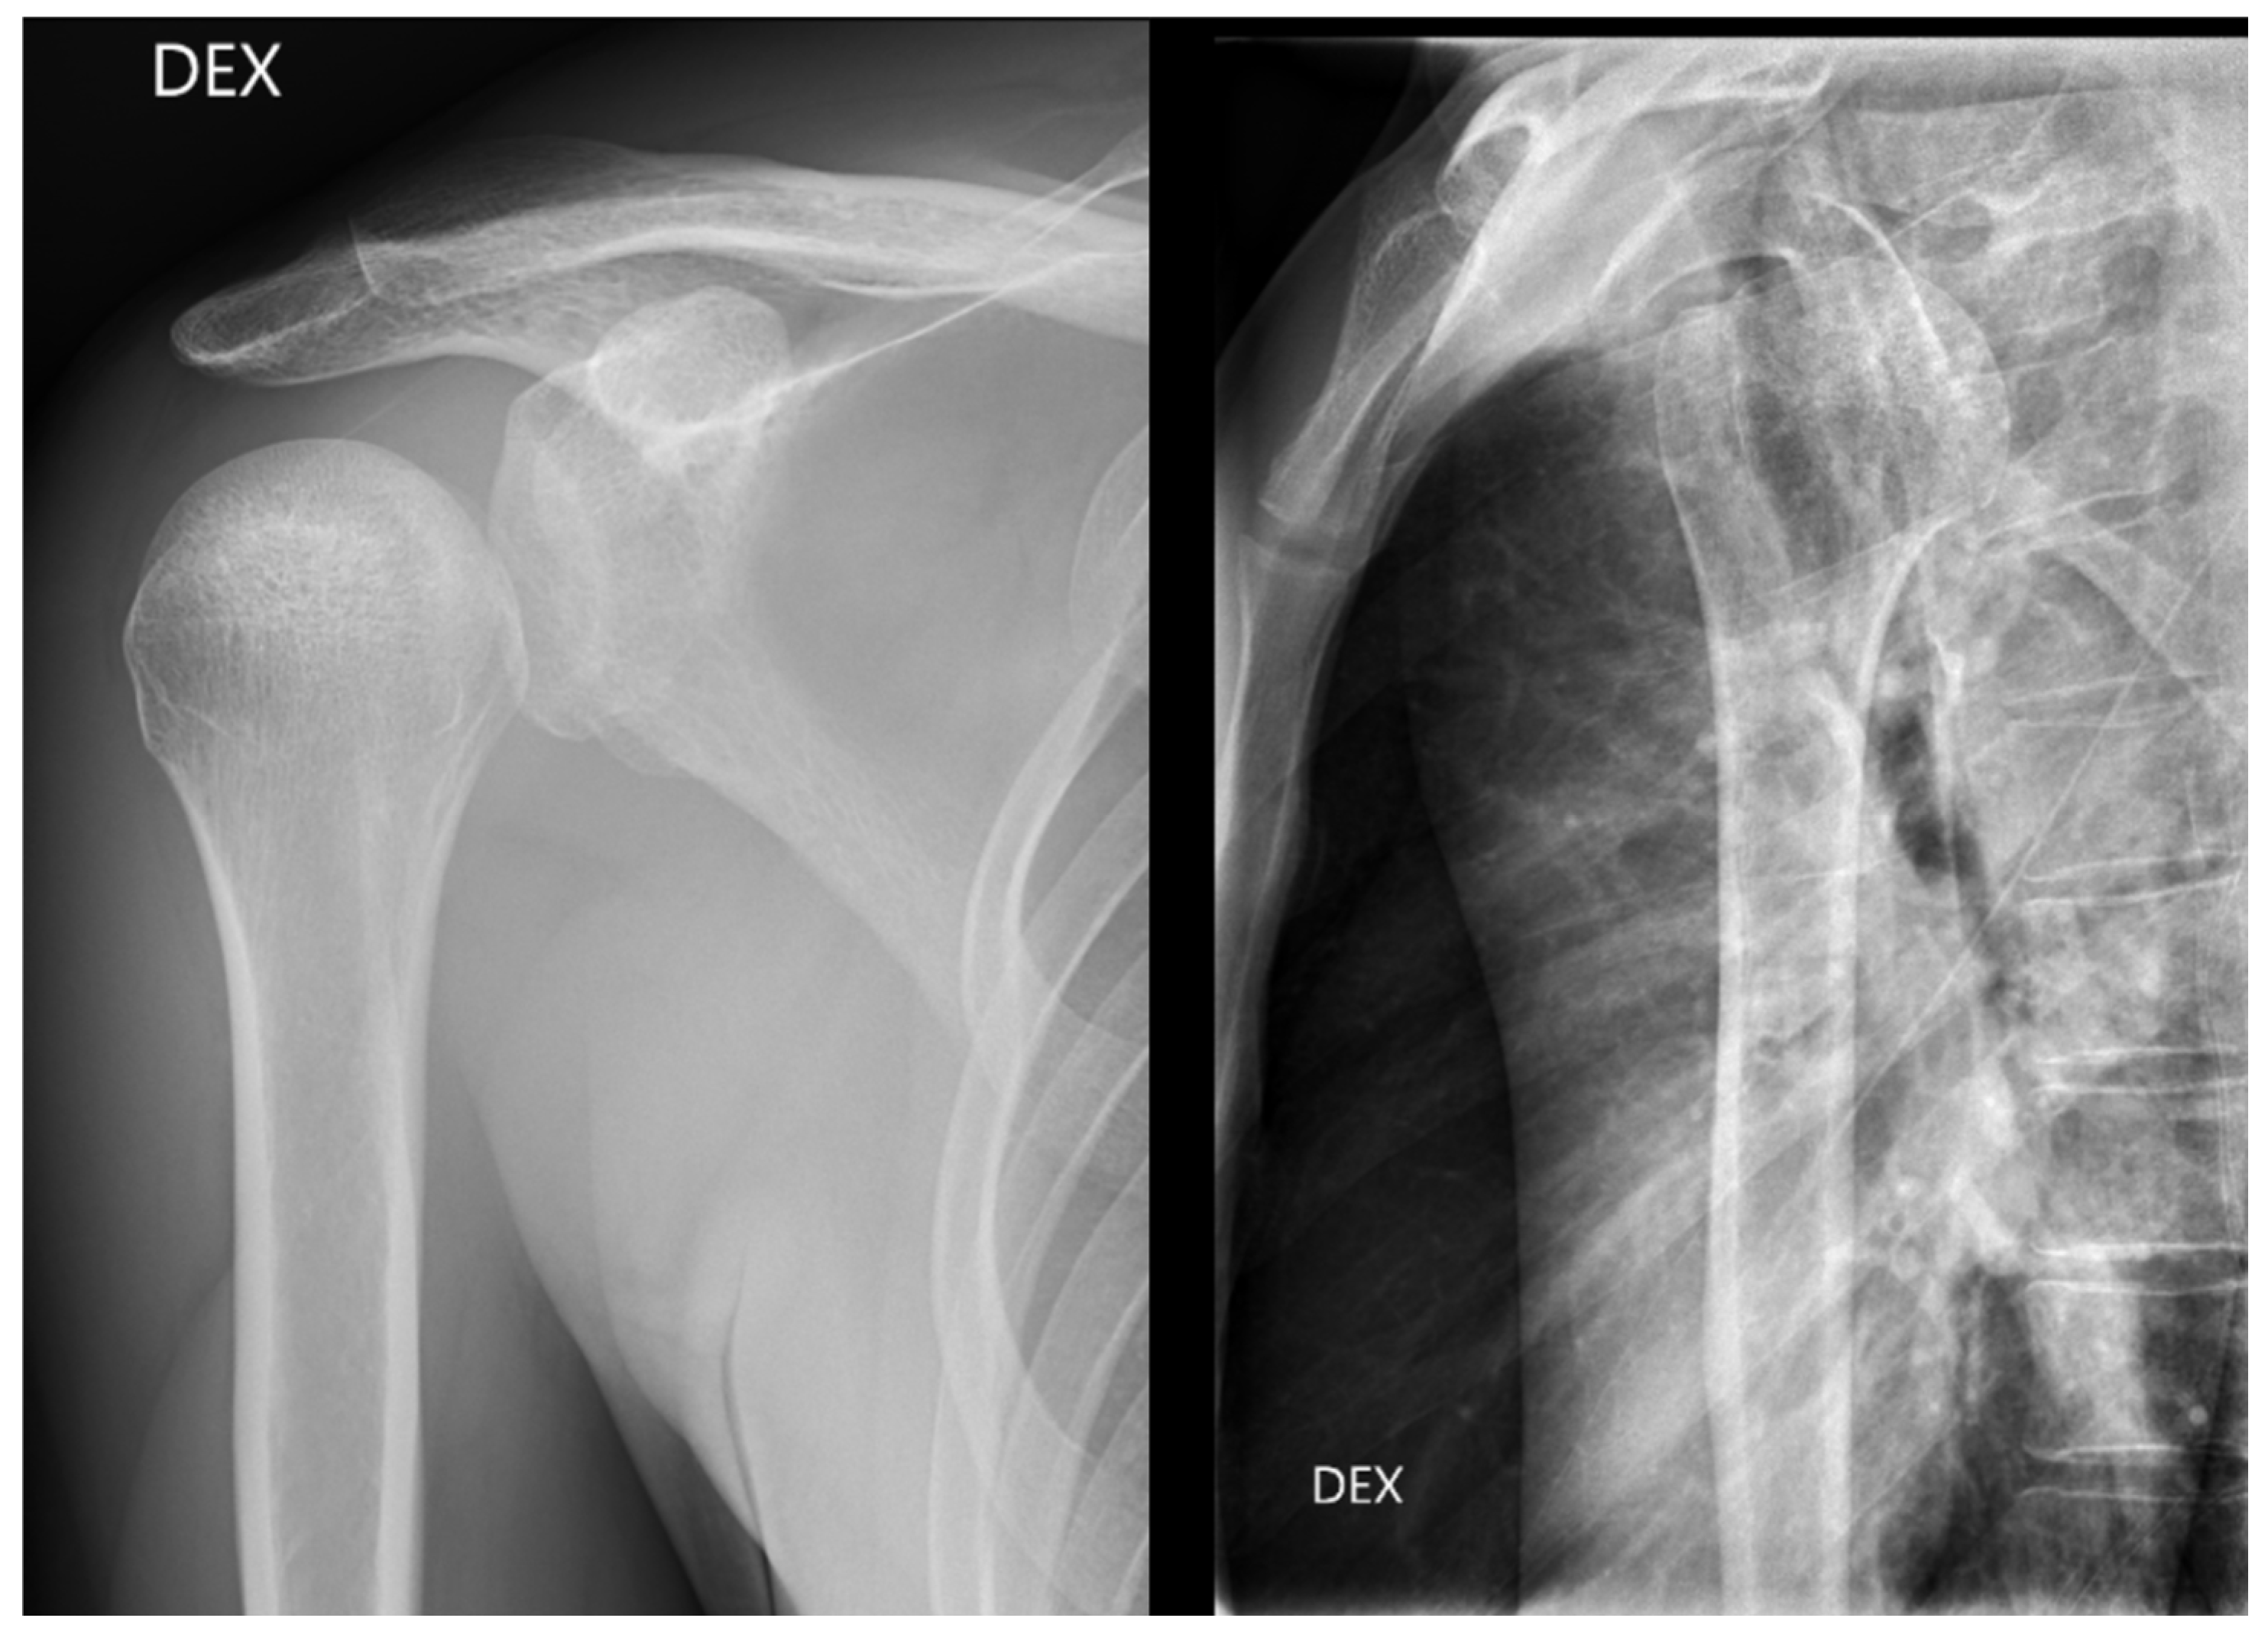

From all the missed findings in the radiographs, 70% (n = 44) were interpreted as having an impact on patient care (p = 0.02), but this did not differ between the radiology specialists and the residents. Findings missed by the radiology specialists (Figure 4 and Figure 5) affected patient care in 71% of cases and overcalls in 31% of cases. Findings missed by the residents (Figure 6) affected patient care in 69% of cases and overcalls in 47% of cases. From all the overcalls in the radiographs, 40% (n = 12) seemed to have an impact on patient care. The most common impact on patient care was a lack of the necessary control study (40%), followed by an unnecessary control study (14%). Interpretation error rarely led to unnecessary operative treatment (1%).

Figure 4.

Posterior dislocation initially missed by the radiology specialist. The treating physician later suspected GH dislocation on clinical inspection, and a CT was ordered where posterior dislocation was detected.